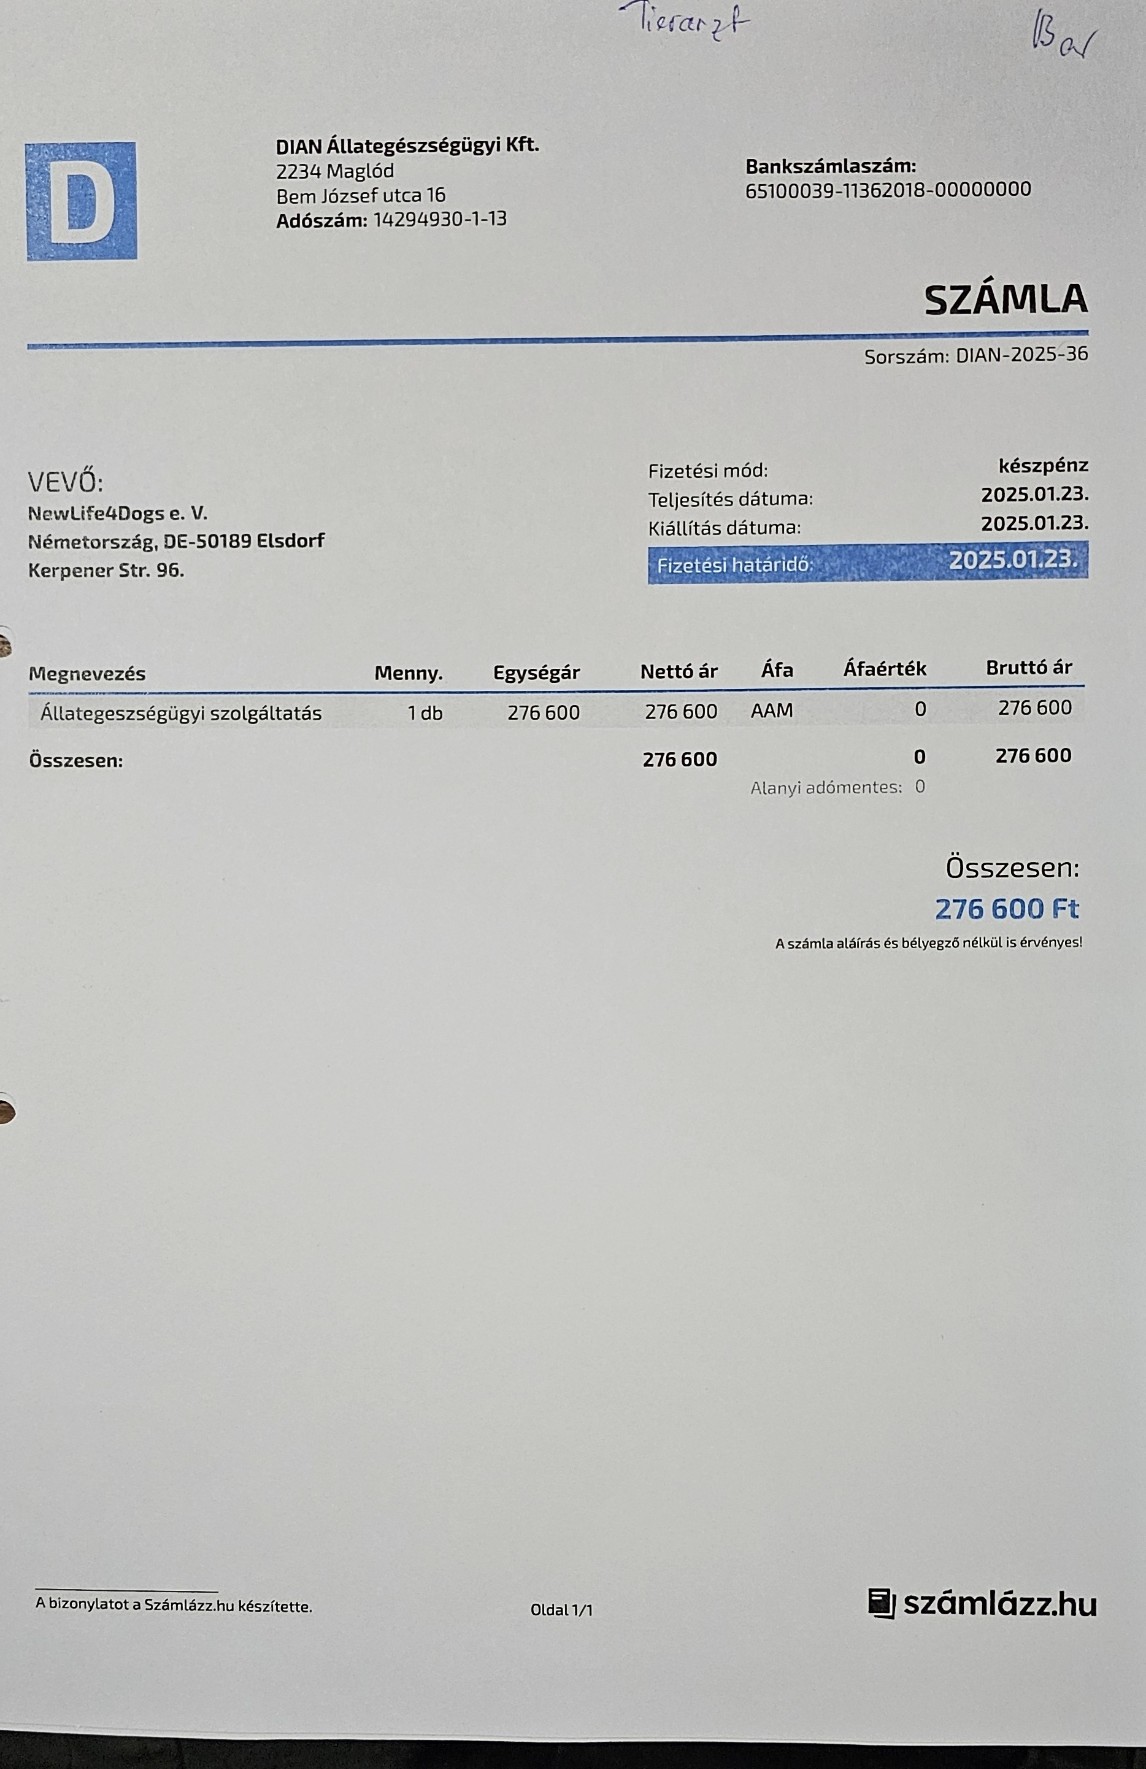

Nachdem die kleine Stella nach mehr als einer Woche die Klinik verlassen durfte, Mussten erneut einige unserer Neuzugänge dringende Not-OP´s und stationäre Aufnahme +ber sich ergehen lassen. So auch der kleine Sidney, den wir schwer verletzt mit gebrochenem Hinterbeinchen auf der Strasse in Nordungarn fanden. Sofortige Untersuchungen, Rüntgenaufnahmen und unverz+gliche Notoperation war erforderlich. Die Operation hat der kleine Mann gut überstanden. Nun benütigt er weitere Medikamente und Vitaminprodukte, damit er einen guten Heilungsprozess durchlaufen kann. Ebenso benütigt er 6 Wochen Zwingerruhe und Physiotherapie.

Auch hier in Örkény wurden wir zu einer schwerst verletzten Hündin gerufen. Blutüberströmt fanden wir die Hündin vor einem hiesigen Geschäft liegend auf. Der Inhaber des Geschäftes kümmerte sich bis zu unserer Ankunft um die Hündin, Da sie in ihrem Zustand und dem hohen Blutverlust die Fahrt bis zu Klinik nicht überstanden hätte ließen wir den hiesigen Tierarzt zu Notversorgung kommen. Die weitere Behandlung kann nun hier erfolgen und uns bleibt nur zu hoffen, das sie diese Verletzungen überleben wird. Natürlich werden wir auch für diese Hündin alles tun und unser bestes geben.

Auch unser lieber Oskar musste heute notfallmäßig in die Tierklinik. Aus derzeit noch unerklärlichen Gründen kann oskar sich nicht mehr auf seinen Hinterbeinen halten. Natürlich brachten wir ihn sofort in die Klinik. dort wurde er stationär aufgenommen. Nun ist eine MR untersuchung erforderlich, um die Ursache f+r die plützlichen Lähmungserscheinungen zu finden. Auch in der zweiten hälfte des Monats mussten wir wieder hohe Klinikkosten und Tierarztkosten bewältigen. Wir wären extrem erleichtert und dankbar wenn uns der ein oder andere hierbei unterst#tzen würde.